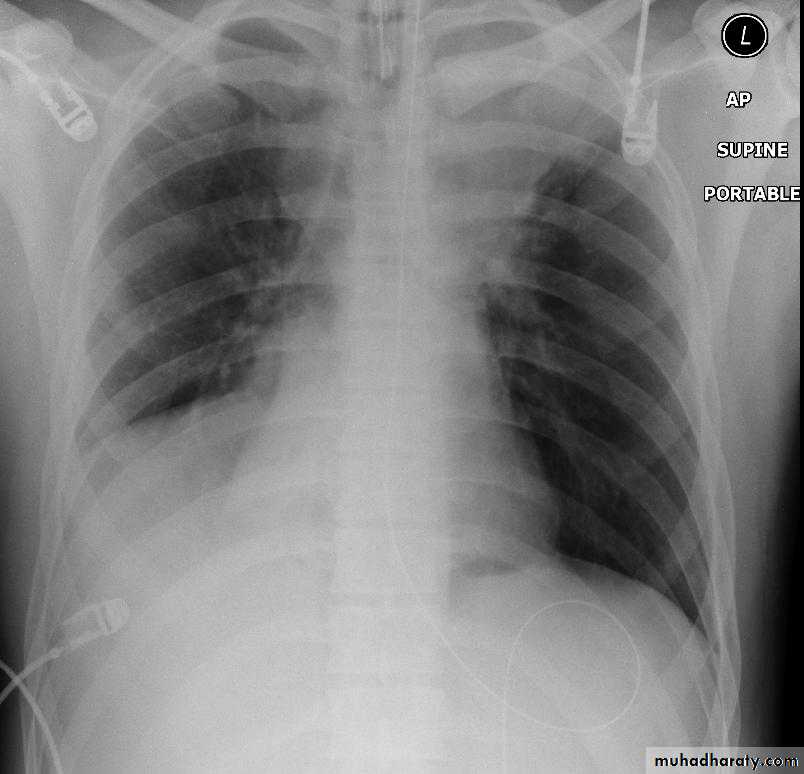

Left lower lobe collapse has distinctive features, and can be readily identified on frontal chest radiographs, provided attention is paid to the normal cardiomediastinal contours. The shadow cast by the heart does however make it harder to see than the right lower lobe collapse

Radiographic features

Left lower lobe collapseis readily identified in a well penetrated film of a patient with normal sized heart, but can be challenging in the typical patient with collapse, namely unwell patients, with portable (AP) often under-penetrated films, often with concomitant cardiomegaly. Features to be observed include :

triangular opacity in the posteromedial aspect of the left lung

edge of collapsed lung may create a 'double cardiac contour'

left hilum will be depressed

loss of the normal left hemidaphgragmatic outline

loss of the outline of the descending aorta

Non-specific signs indicating left sided atelectasis are usually also be present including:

elevation of the hemidiaphragm

crowding of the left sided ribs

shift of the mediastinum to the left

On lateral projection the left hemidiaphragmatic outline is lost posteriorly and the lower thoracic vertebrae appear denser than normal (they are usually more radiolucent than the upper vertebrae) .